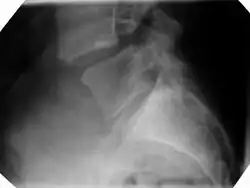

Kręgozmyk (łac. spondylolisthesis z gr. σφόνδυλος spóndylos "kręg", ὀλίσθησις olísthēsis "ześliźnięcie") – przemieszczenie kręgów wraz z całym odcinkiem kręgów wyżej leżących ku przodowi w stosunku do kręgu położonego niżej. Powstaje wskutek istnienia szczeliny łuku kręgowego w miejscu połączenia wyrostków stawowych górnego i dolnego. Kręgozmyk najczęściej występuje w dolnym odcinku kręgosłupa lędźwiowego. Choroba objawia się bólami promieniującymi do kończyn dolnych, nasilającymi się przy siadaniu i wstawaniu. W późniejszym czasie dochodzą trudności w poruszaniu się chorego z uwagi na ucisk na korzenie nerwowe. Leczenie polega na przywróceniu stabilności kręgów na drodze zachowawczej lub operacyjnej. Na kręgozmyk chorują dzieci, młodzież i dorośli[1].